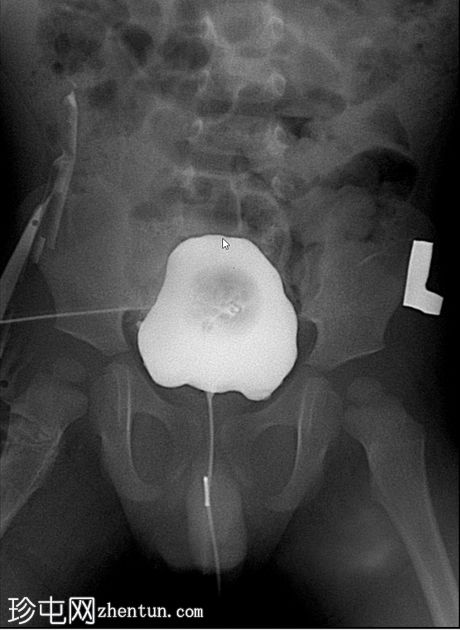

排尿影像

使用纱布进行外部压迫成功阻塞了脐尿管开口,膀胱充盈良好。左侧输尿管和肾盂肾盏系统可见膀胱输尿管反流,符合II/III级VUR。输尿管轮廓正常,无憩室,无管壁增厚。尿道显影正常,未见后尿道瓣膜或狭窄。无肾积水。